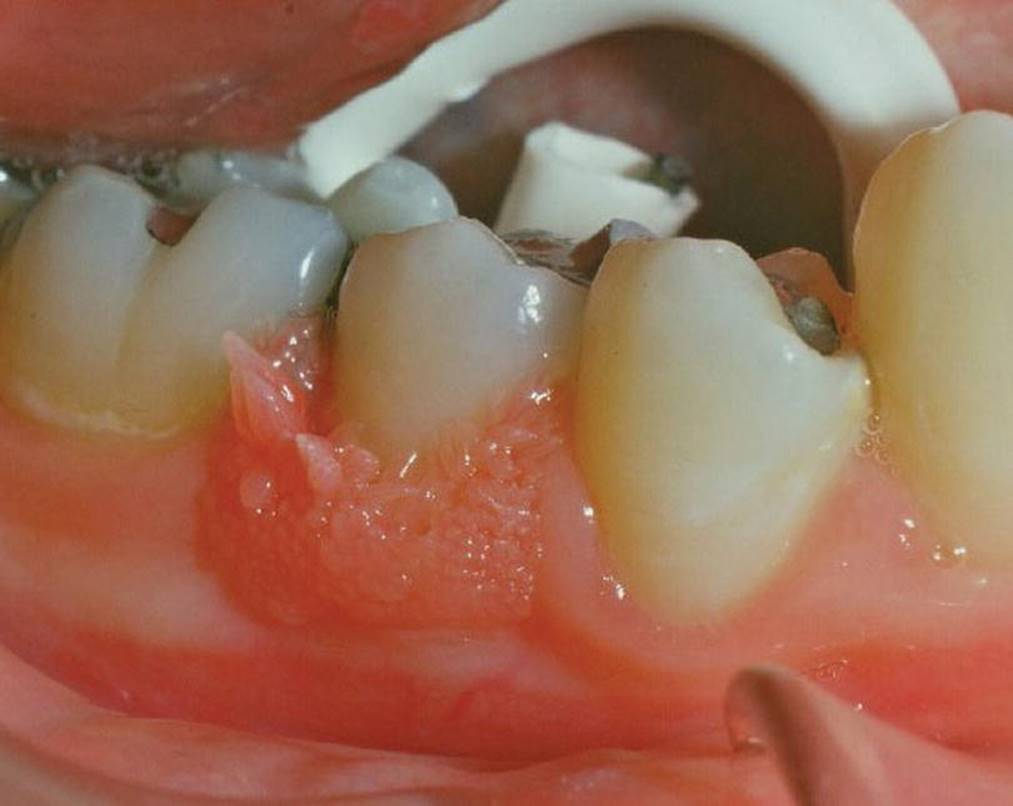

Epulides are by definition tumor‐like hypertrophic tissue formations located on the gingival mucosa. The etiology is often trauma or irritation in connection with tooth eruption or exfoliation. The size may vary from some millimeters up to several centimeters in diameter. They differ in surface texture, consistence and color, depending on the tissue composition. Pyogenic granuloma, peripheral calcifying granuloma, and peripheral giant cell granuloma (Figures 15.19, 15.20 and 15.21) are all examples of epulides. The treatment is excision, and the final diagnosis is confirmed by histopathologic analysis.

Figure 15.19 Pyogenic granuloma.